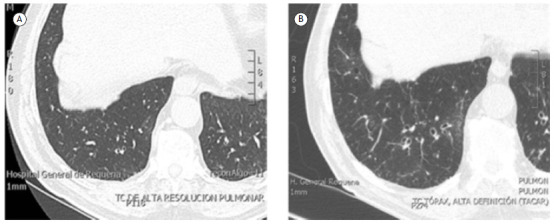

Abstract Image